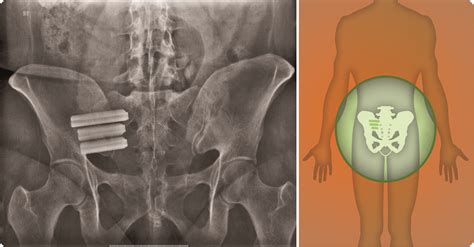

The most common and effective procedure for addressing SI joint pain is minimally invasive SI joint fusion. Unlike traditional open back surgeries that required large incisions and long hospital stays, modern Si Joint Surgery is performed using small incisions and specialized implants.

3. Implant Placement: Guided by fluoroscopy (real-time X-ray imaging), the surgeon places titanium implants across the SI joint to bridge it.

4. Fusion: These implants hold the joint in a fixed, stable position, allowing the body to naturally grow bone across the joint, permanently fusing it.